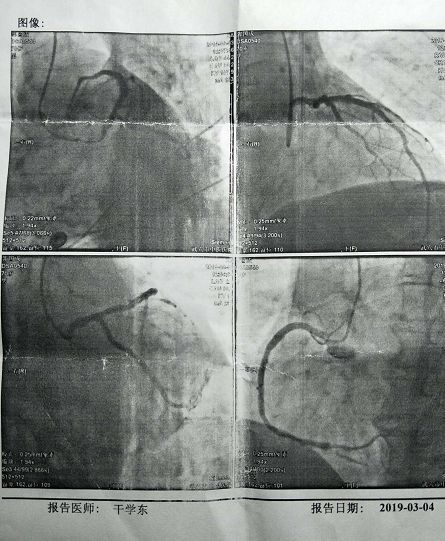

許多高血壓、冠心病、心衰、心律失常等心臟病患者來(lái)中醫(yī)院求醫(yī),絕大多數(shù)是沖著“三劍客之一——業(yè)務(wù)副院長(zhǎng)程航的名氣而來(lái)的。程航曾被評(píng)為“黃岡市十佳滿意醫(yī)生,是位德藝雙馨的好醫(yī)生。根據(jù)病情,程航和主治醫(yī)師郭威雙竿齊下,很快給我拿出了診治方案:一邊上組合點(diǎn)滴,用抗生素控制肺部及支氣管的炎癥,減緩胸閉呼吸困難,一邊約請(qǐng)中南醫(yī)院心內(nèi)科專(zhuān)家干學(xué)東來(lái)院作造影檢查,以確診是否是PCl后冠動(dòng)脈再次堵塞。這若是以往,作造影這種高科技高難度檢查,非得去武漢不可,如今中醫(yī)院添置了造影機(jī),通過(guò)培訓(xùn)進(jìn)修,基本掌握了心臟介入治療技術(shù),加上上級(jí)聯(lián)合體醫(yī)院定期派專(zhuān)家來(lái)坐診,在家門(mén)口就可以做這種檢查,真是方便又省錢(qián)!當(dāng)天與我同時(shí)預(yù)約造影檢查和植支架手術(shù)的有20人。去年,該院共為冠心病病人作造影和安裝支架達(dá)幾千人次。

周日上午十點(diǎn),一大早從武漢趕來(lái)的干教授來(lái)不及歇息就走進(jìn)手術(shù)室導(dǎo)管室。我被安排第三個(gè)進(jìn)導(dǎo)管室,沒(méi)有恐懼,也不緊張,因?yàn)檫@已經(jīng)不是頭部次了。了解這種微創(chuàng)手術(shù),造影手術(shù)全在血管內(nèi)進(jìn)行,而血管組織又沒(méi)神經(jīng),所以手術(shù)過(guò)程沒(méi)一絲疼痛。右手腕局部麻醉,橈動(dòng)脈穿刺,插鞘管,注射造影劑……前后不到半小時(shí),干教授那“行云流水”般的造影術(shù),猶如魔術(shù)大師將秘密深處的冠狀動(dòng)脈清晰地呈現(xiàn)在顯示屏上……

焦急的等待著,終于等到了干教授的診療報(bào)告:1、左主干血管正常,支架內(nèi)無(wú)狹窄,回旋支近段支架內(nèi)無(wú)狹窄;2、右冠狀動(dòng)脈支架內(nèi)無(wú)狹窄,根據(jù)造影圖像。干教授認(rèn)為沒(méi)必要植入支架,調(diào)整藥物進(jìn)行后期治療。走出手術(shù)室,懸在心上的一塊石頭終于放下了。